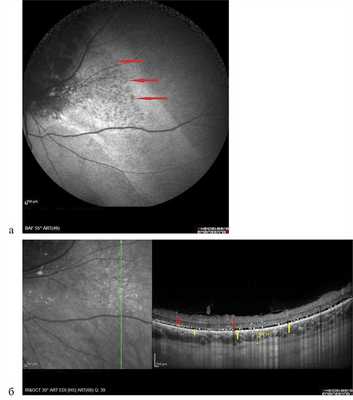

Гемангиома хориоидеи характеризовалась выраженными отличительными признаками как при проведении ангиографии с индоцианином зеленым, так и при УЗИ с ЦДК. Данную патологию отличали идентификация патогномоничных сосудистых паттернов в виде рисунка «рыбацкой сети», сети в виде «кружева» и гиперфлюоресценция на всех фазах исследования (рис. 5, а, б). При проведении УЗДГ выявлялся высокоскоростной и среднерезистентный кровоток (рис. 5, в).

Рис. 5. Гемангиома хориоидеи при ангиографии с индоцианином зеленым.

а, б — сосудистые паттерны в виде рисунка «рыбацкой сети», сети в виде «кружева» и гиперфлюоресценция на всех фазах исследования; в — УЗДГ-картина: высокоскоростной и среднерезистентный кровоток в ткани опухоли (размер образования 1,8×9,2 мм).